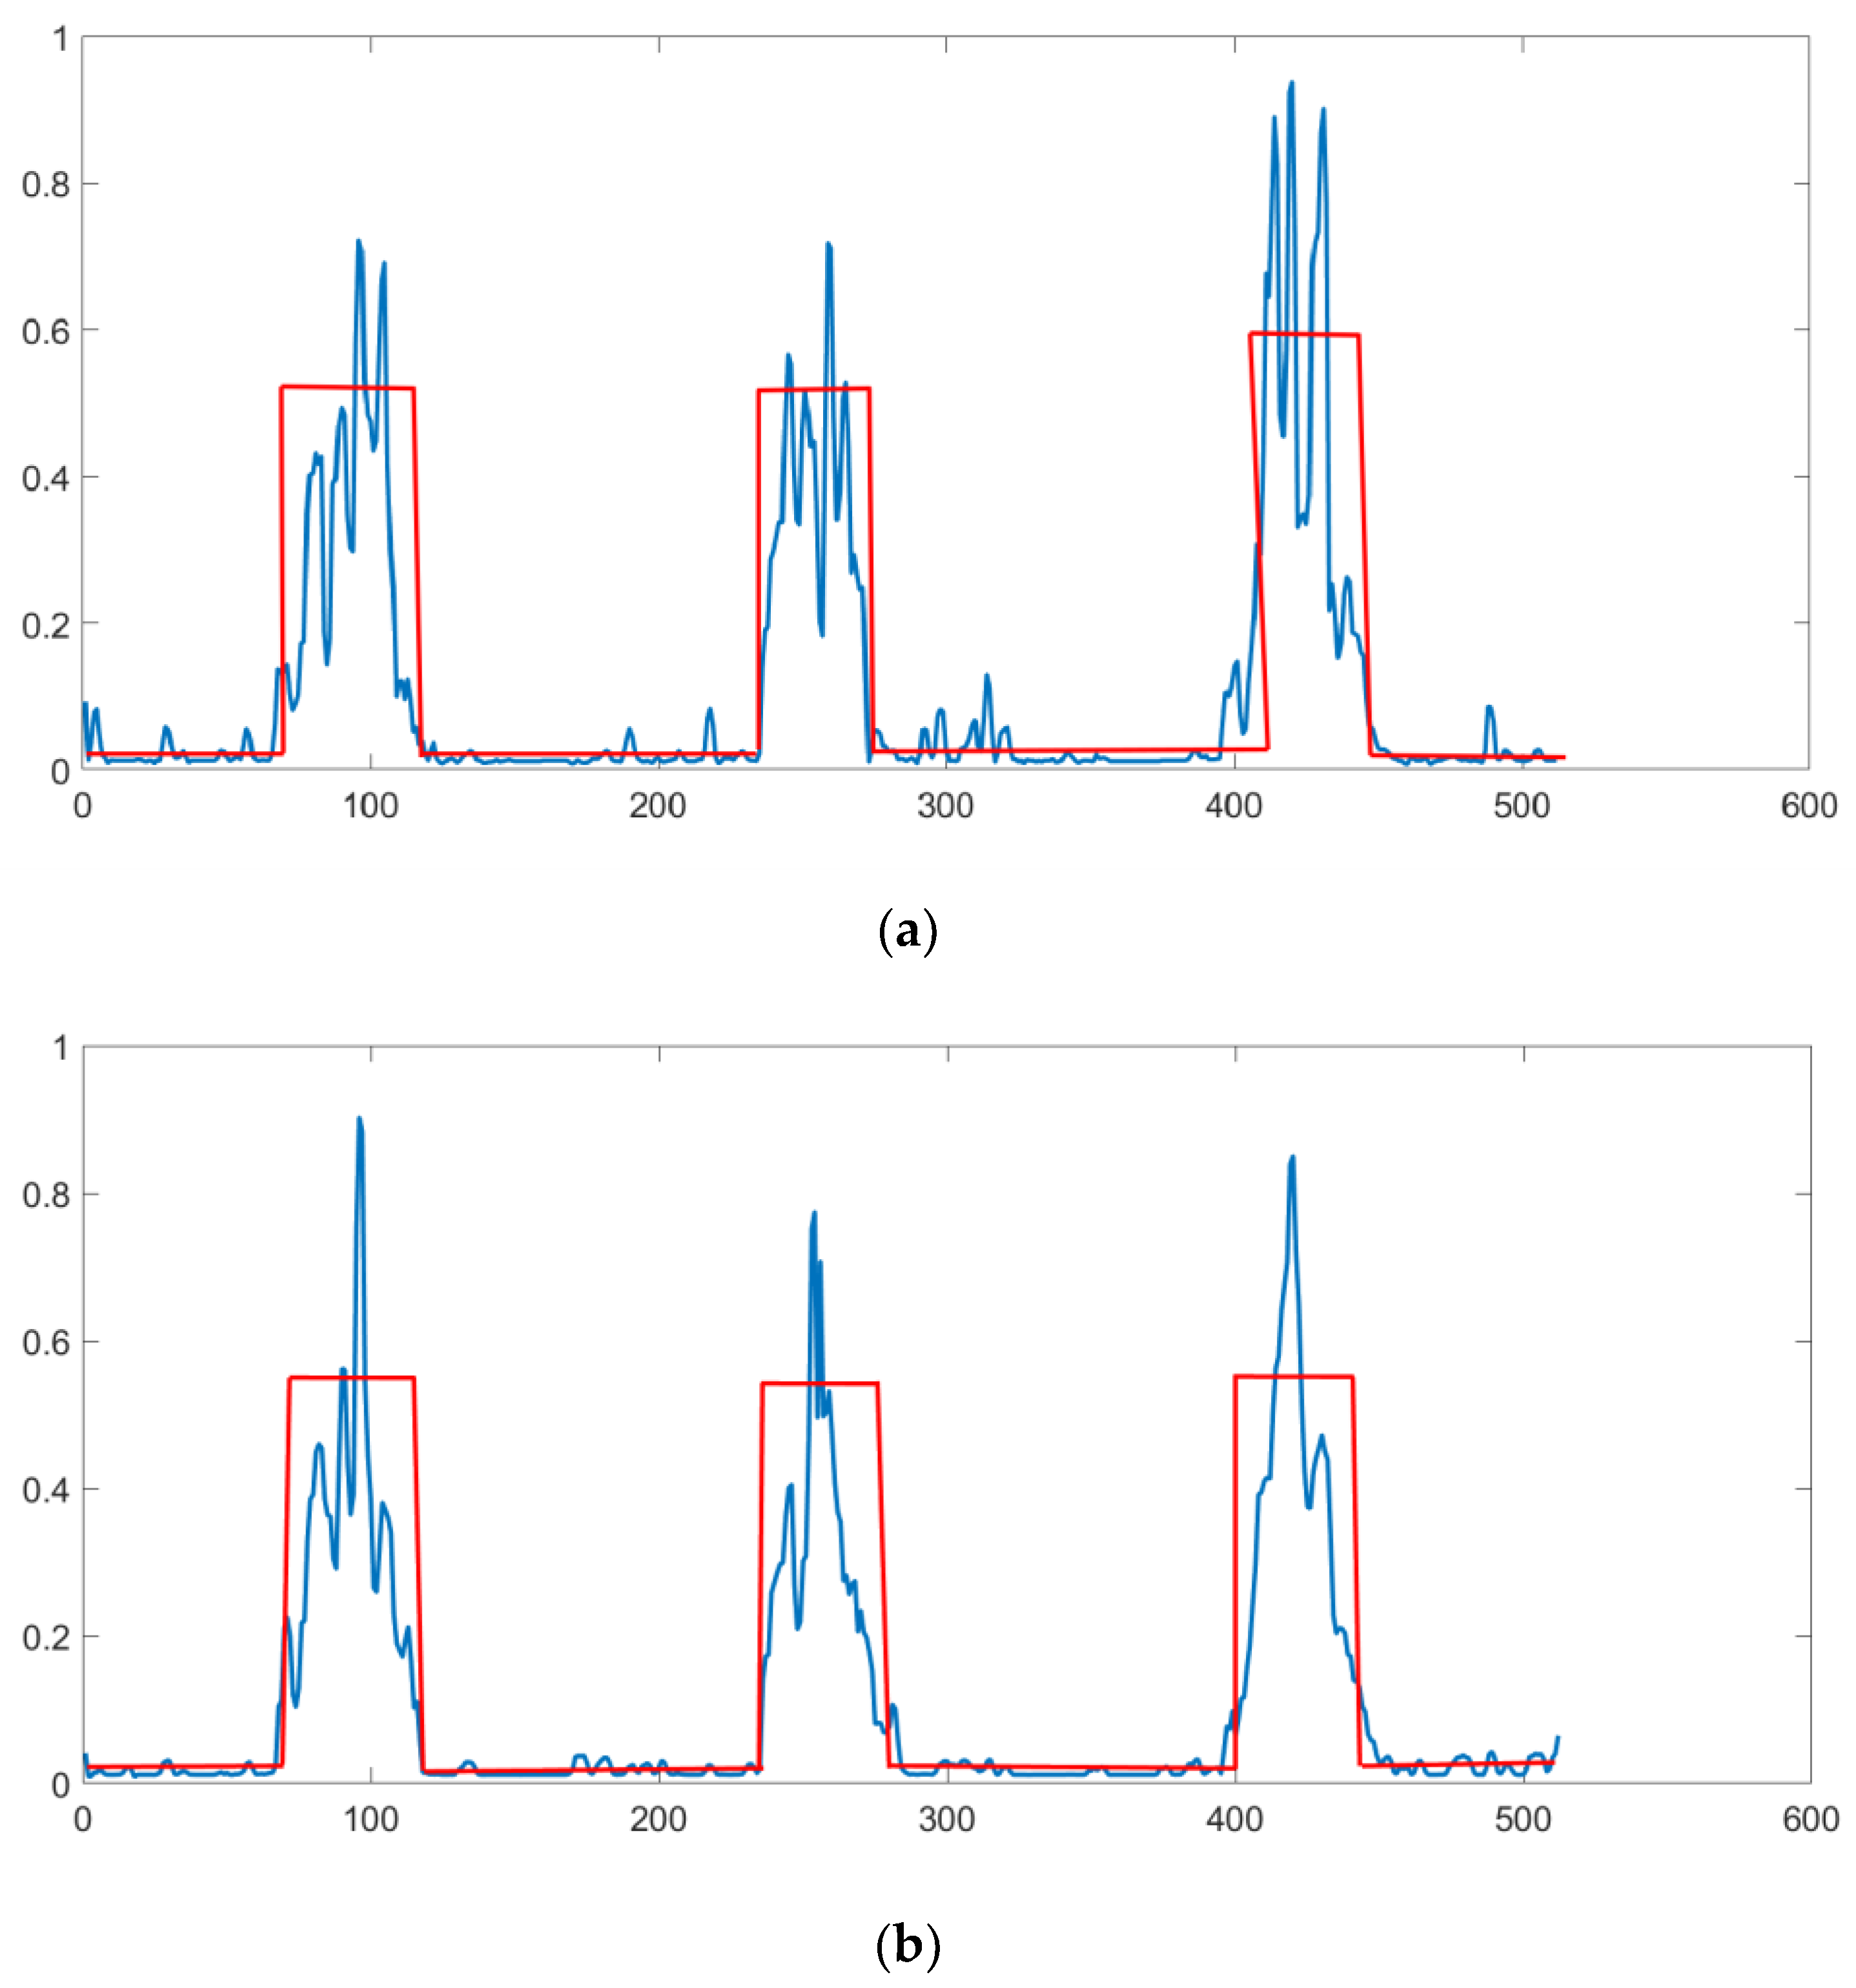

3. Results

4. Discussion